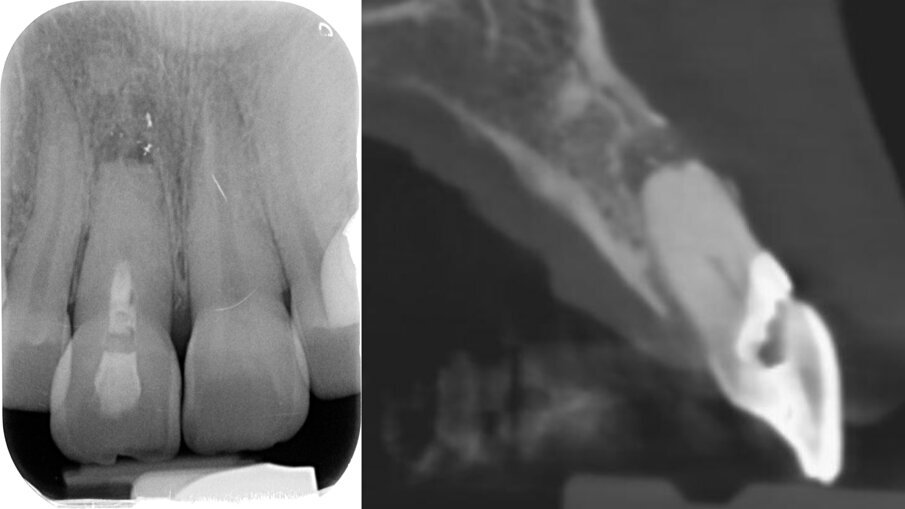

All’esame obiettivo generale la paziente presenta una malocclusione di 2a classe con recessioni multiple dei settori frontali e lateroposteriori, un sorriso gengivale e un fenotipo gengivale sottile e festonato con denti di forma triangolare, mentre a livello locale il dente 1.1 si presenta fortemente discromico con fistola apicale, recessione dei tessuti molli sia del 1.1 che del 2.1 di circa 3 mm con erosione cervicale (Fig. 2). Una prima indagine radiografica bidimensionale (rx endorale periapicale) evidenzia sul 1.1 una terapia canalare incongrua e radiotrasparenza apicale. Un esame tridimensionale CBCT evidenzia la discontinuità della corticale vestibolare identificata come classe 4 secondo Tarnow4, come esito dell’infezione apicale, ma rimane un ponte osseo crestale che sarà fondamentale per il percorso di ricostruzione dei tessuti duri e molli (Fig. 3).